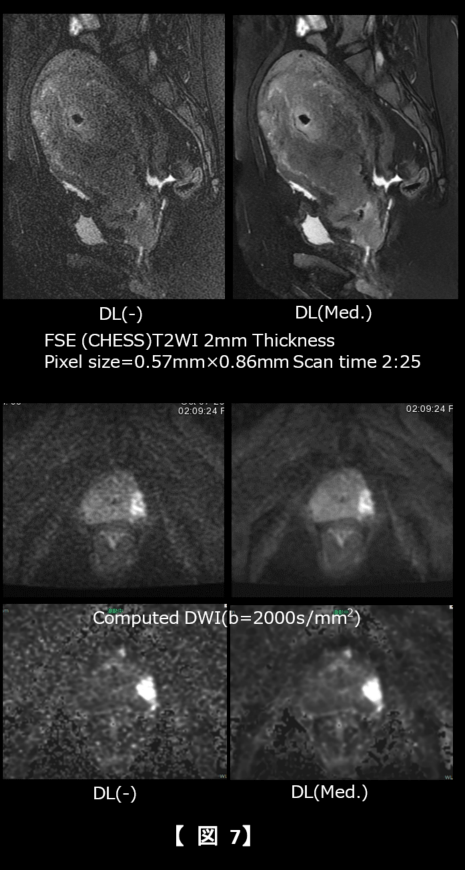

骨盤部領域においても、短時間で撮像することにより呼吸性Artifactの低減と低下するSNRを持ち上げることによりCubeに勝くらいの画質で撮像することが可能であった(図7上段)。前立腺DWIにおいては、cDWI画像においても元になるDWI画質が向上することによる効果が明瞭となった(図7中、下段)。